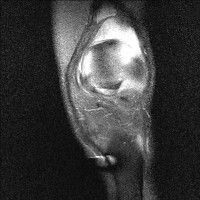

무릎 mri 간단히 봐주실 수 있으시나요 ㅠㅠ

안녕하세요 8년전 십자인대 수술하고 최근 무리한 운동에 무릎 불편감이 생겨서

mri 찍었습니다.

진단결과는 첫 찍은 병원에서 활액막염 이라는 진단을 받았습니다. 혹시 봐주실 수 있으실까요?

올라온 MRI가 단편적이라서 정확한 진단에 어려움이 있지만 십자인대에는 큰 이상이 있지는 않은것 같으며, 무릎관절내 물이 있는 것으로 보아 활액막염의 진단이 맞을 것 같습니다.

하지만 단편적인 영상이기 때문에 촬영병원에서 정확한 판독지 등을 받으시는 것이 좋겠습니다.